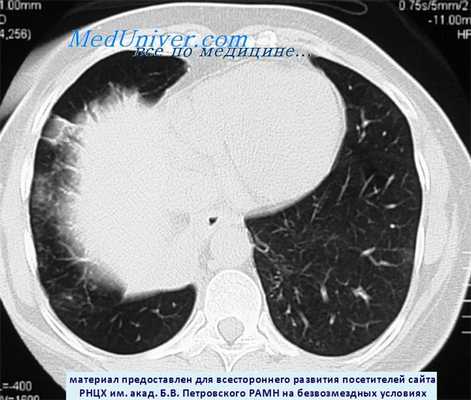

КТ при карциноиде нижней доли правого легкого